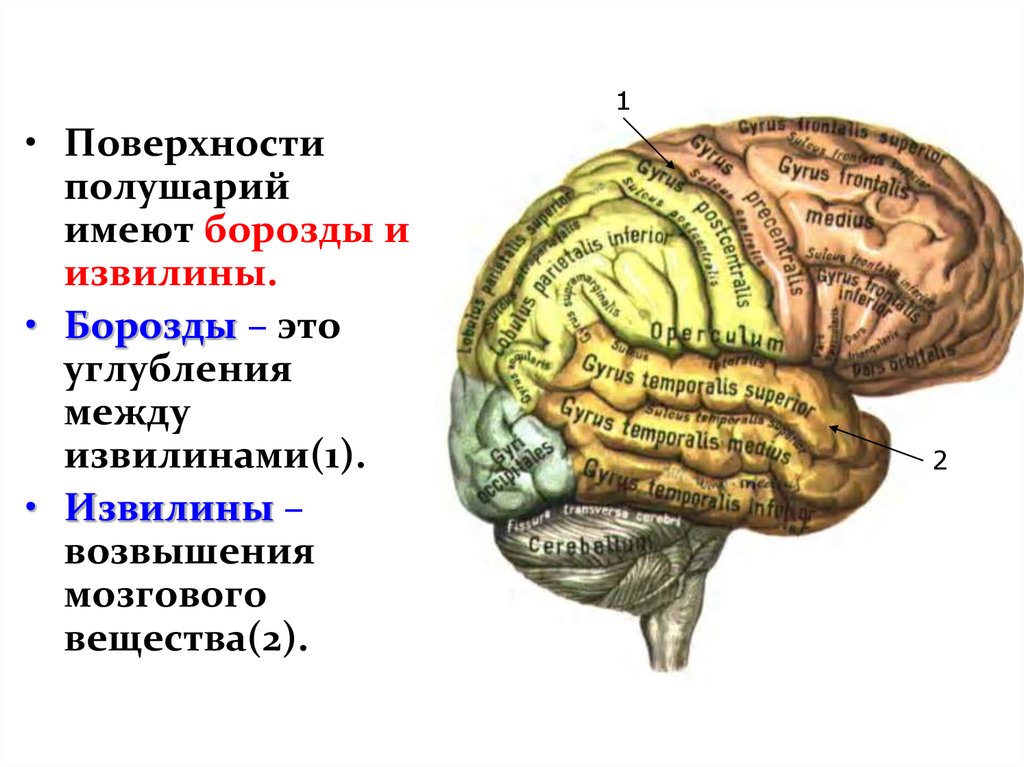

Анатомические снимки верхнелатеральной поверхности головного мозга